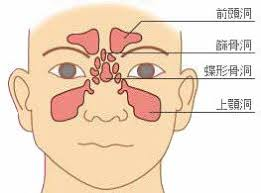

上顎洞とは?

上顎洞(じょうがくどう)とは、上顎骨の中にある空洞で鼻とつながっています。鼻の周りには4つの空洞(副鼻腔)がありそれぞれ上顎洞、篩骨洞(しこつどう)、前頭洞(ぜんとうどう)、蝶形骨洞(ちょうけいこつどう)と呼ばれています。

体の中の空洞に化膿性の炎症が起きて、膿汁がたまることを蓄膿とよびます。一般的に蓄膿症と呼ばれているものは、副鼻腔内に膿汁がたまってしまう副鼻腔炎です。副鼻腔の上顎洞の中に炎症が起きてしまうものを上顎洞炎と呼んでいます。ソケットリフトは、上顎洞の中を処置しますので、上顎洞内に細菌感染や異物の混入などのリスクを伴います。しかし、赤羽歯科 新宿診療所では、必要に応じて、事前に抗生物質(ジスロマック)の服用をし、感染予防を行います。また、ソケットリフトの際に使用する材料は、生体親和性の高いものを使用し、拒否反応の軽減をはかります。赤羽歯科では、ソケットリフトやインプラント治療を行うときは、通常の歯科治療より滅菌レベルの高いオペ室を完備していますので、感染リスクを最小限に抑えて処置することができます。